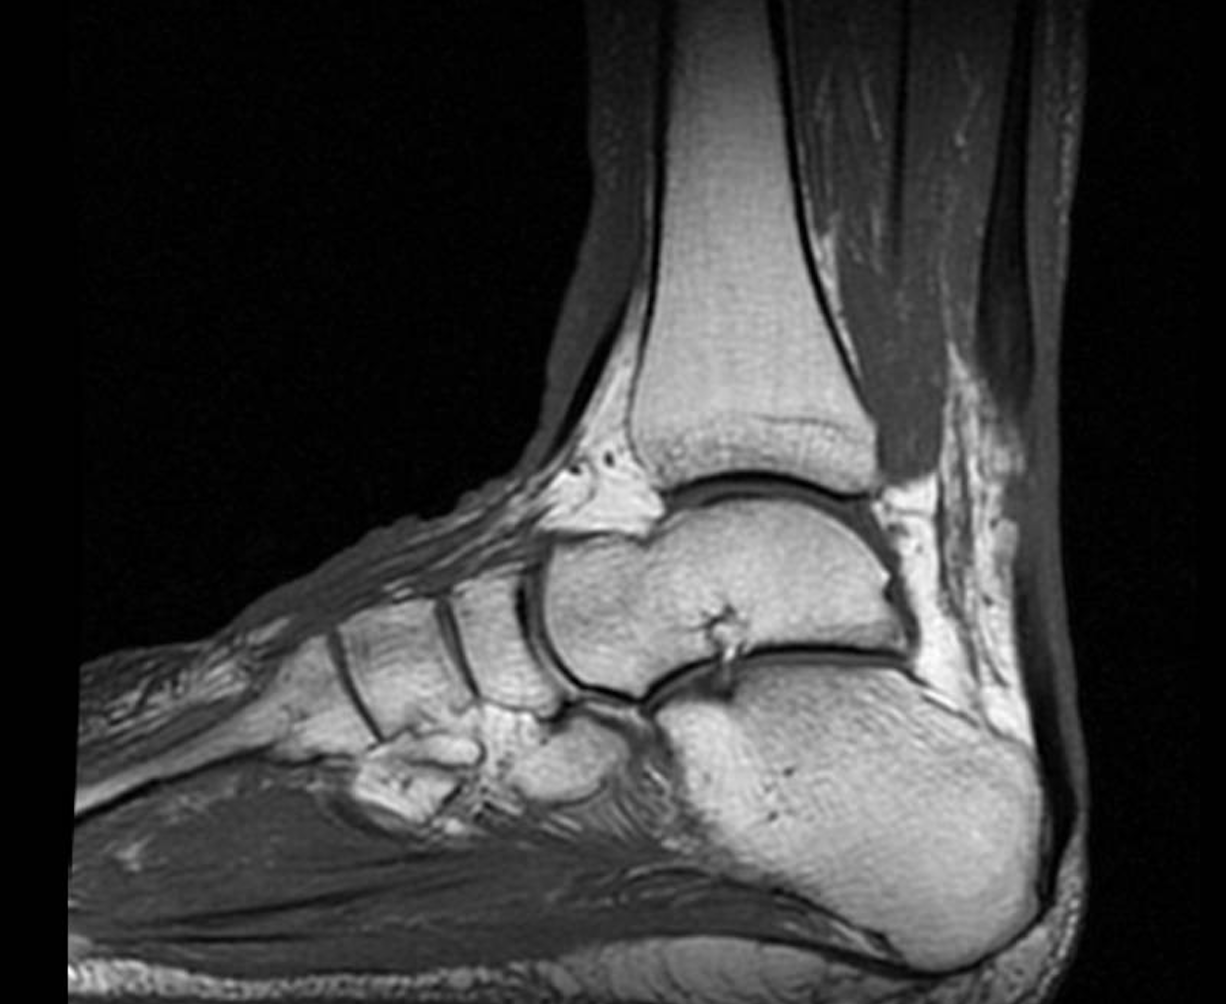

A physical exam revealed edema bilateral to the lower extremities with ecchymosis on the left side but not on the right lower extremity. The patient was neurovascularly intact, and the exam revealed a positive Thompson test on the bilateral lower extremities with no active ankle plantarflexion on the left and right sides. There was a palpable delve in the Achilles on both sides. An MRI that day on both lower legs revealed bilateral Achilles tendon ruptures with a left gap of 3.5cm and a right gap of 2.5 cm.